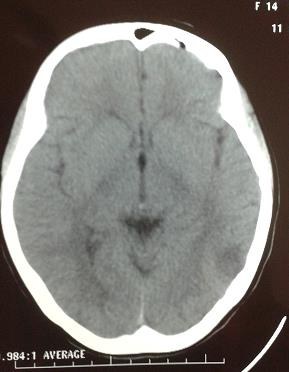

• Leucoencefalopatía Posterior Reversible post eclampsia

Anabela Fernández, Jorge Castelli, Julio Citera, Risel Suárez, Anela De Armas, Gladys Germano, Martín Mojoli

41-45

DOI: https://doi.org/10.35954/SM2015.34.1.6